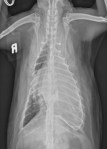

Latérale gauche